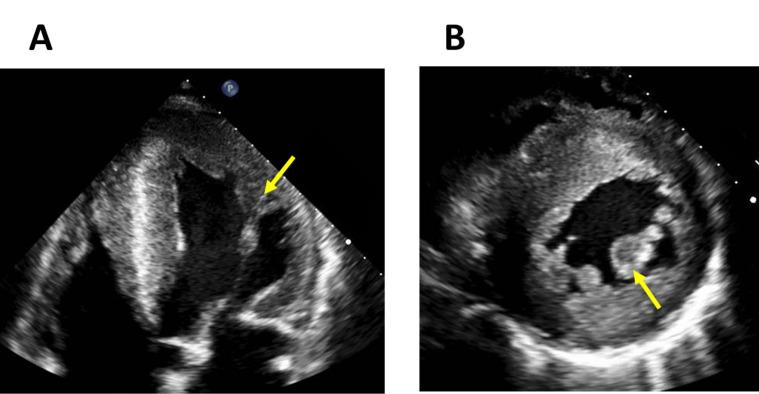

法布里病心肌病:从诊断到治疗的心脏成像作用综述

Fabry Disease Cardiomyopathy: A Review of the Role of Cardiac Imaging from Diagnosis to Treatment.

Fabry disease is a rare X-linked inherited lysosomal storage disorder caused by the absence or reduction of alfa-galactosidase A activity in lysosomes, resulting in accumulation of glycosphingolipids in various tissues. The main organ affected is the heart, which frequently manifests as left ventricular hypertrophy and can ultimately lead to cardiac fibrosis, heart failure, valve disease, cardiac conduction abnormalities and sudden cardiac death. Today we know that myocyte damage starts before these signs and symptoms are detectable on routine studies, during the designated pre-clinical phase of Fabry disease. The initiation of specific therapy for Fabry disease during the early stages of the disease has a great impact on the prognosis of these patients avoiding progression to irreversible fibrosis and preventing cardiovascular complications. Cardiac imaging has become an essential tool in the management of Fabry disease as it can help physicians suspect the disorder, diagnose patients in the early stages and improve outcomes. The recent development of novel imaging techniques makes necessary an update on the subject. This review discusses the role of multimodal imaging in the diagnosis, staging, patient selection for treatment and prognosis of Fabry disease and discusses recent advances in imaging techniques that provide new insights into the pathogenesis of the disorder and the possibility of novel treatment targets.

摘要

法布里病是一种罕见的X连锁隐性遗传性溶酶体贮积症,由溶酶体中α-半乳糖苷酶A活性缺乏或降低引起,导致糖鞘脂在各种组织中蓄积。主要受累器官是心脏,常表现为左心室肥厚,并最终可导致心脏纤维化、心力衰竭、瓣膜病、心脏传导异常和心源性猝死。如今我们知道,在法布里病的指定临床前期,即常规检查可检测到这些体征和症状之前,心肌细胞就已开始受损。在疾病早期开始对法布里病进行特异性治疗,对这些患者的预后有很大影响,可避免进展为不可逆纤维化并预防心血管并发症。心脏成像已成为法布里病管理中的一项重要工具,因为它有助于医生怀疑该病、在早期诊断患者并改善预后。新型成像技术的最新发展使得有必要对该主题进行更新。本综述讨论了多模态成像在法布里病的诊断、分期、治疗患者选择和预后中的作用,并讨论了成像技术的最新进展,这些进展为该疾病的发病机制和新治疗靶点的可能性提供了新见解。